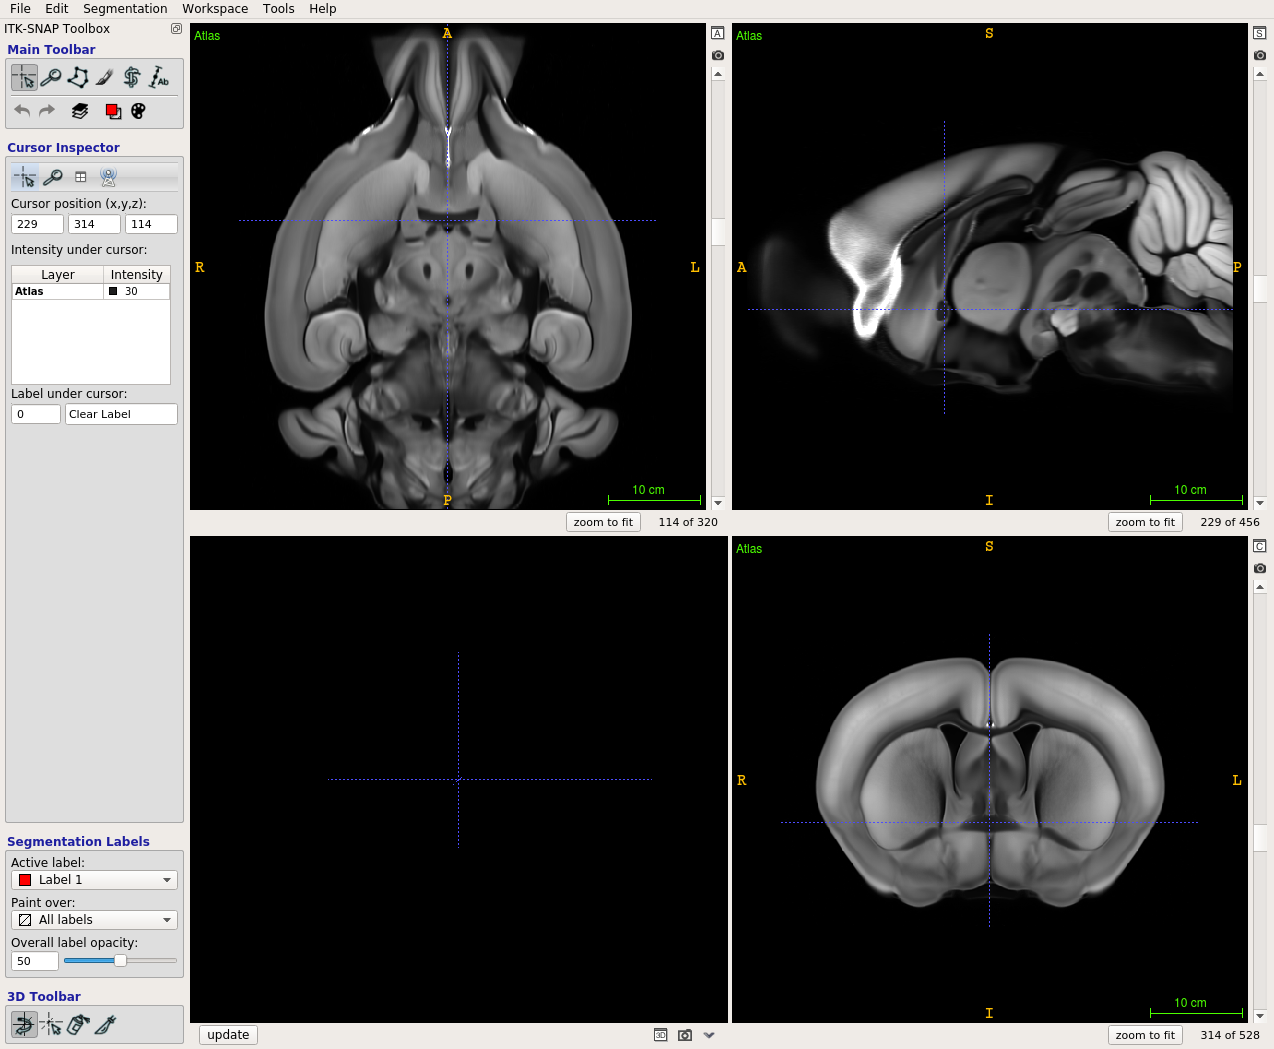

Scalable Brain Atlas  Coronal3d

Mouse - Allen Mouse Brain Common Coordinate Framework version 3

About this atlas

The defining citations for this atlas template are:

1. Lein ES, Hawrylycz MJ, Ao N, et al. (2007) "Genome-wide atlas of gene expression in the adult mouse brain." Nature 445(7124):168-76. [doi 10.1038/nature05453]